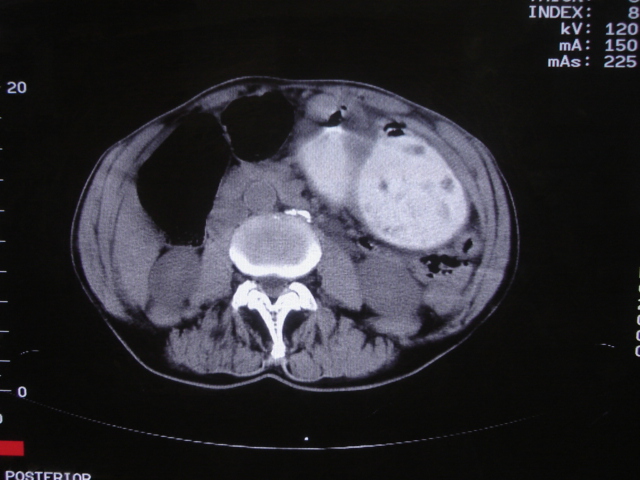

以下是引用前行在2008-7-17 12:57:00的发言:[br]建议胃镱检查

以下是引用杀毒软件在2008-7-17 16:45:00的发言:[br][br] 建议胃镱检查!考虑胃窦部占位